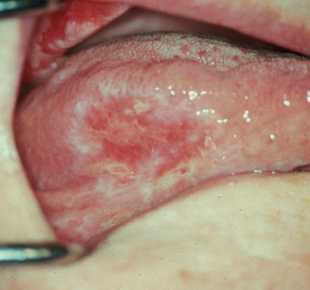

What is erosive lichen planus?

Not as common, painful, erythematous, bleeding

There is no treatment, only palliative. If patients are asymptomatic, do a follow up. If patients are symptomatic, use topical steroids. If a chronic condition, waxes and wanes. <1% may develop cancer

Buccal mucosa, gingiva, tongue, lip